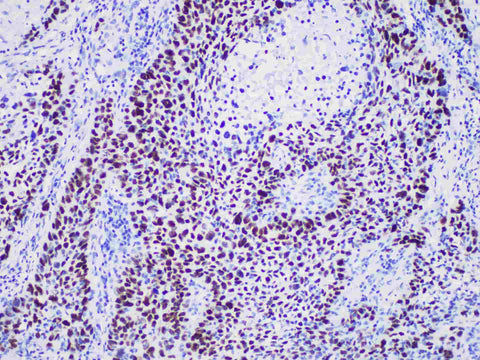

p40 Monoclonal Antibody Stored at 2~8°C

Applications IHC-P

Tissue Specificity lung squamous cell carcinoma

p40 is one of the subtypes of p63 protein. p63 is widely used in the classification of lung cancer in daily pathological diagnosis. It has a high sensitivity in lung squamous cell carcinoma, but it is also partially expressed in lung adenocarcinoma. Therefore, p40 is recommended for the differential diagnosis of lung squamous cell carcinoma and lung adenocarcinoma.